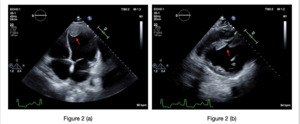

POCUS showed echogenic areas of concern (figures 1a, 1b and 1c) and significantly reduced left ventricular (LV) function by visual estimation and by abnormal E-point septal separation (figure 1d). Due to concern for an LV thrombus, newly diagnosed heart failure, and an NSTEMI, he was started on heparin and diuretics in the ED in consultation with cardiology, and he was admitted to their service for inpatient management. Inpatient echocardiogram showed an ejection fraction of <15% and confirmed two LV thrombi (figure 2a and 2b), the largest measuring 3.35 x 2.8 cm. Left heart catheterization showed disease in the left anterior descending (LAD) and right coronary artery. He subsequently underwent stenting of the LAD and was started on aspirin and clopidogrel. Following optimization of his newly diagnosed heart failure, he was bridged to warfarin for management of his LV thrombus and discharged with Cardiology follow-up.